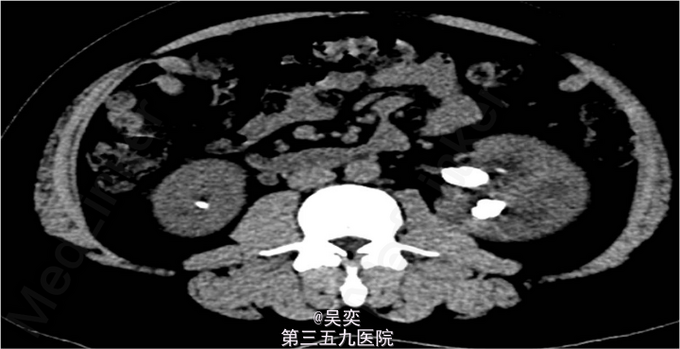

3、查体:无阳性体征 4、辅助检查:我院泌尿系B超:右输尿管上段结石并上段扩张,双肾多发结石。入院后白细胞总数10.550x10E9/L,中性粒细胞绝对值6.970x10E9/L。尿常规:白细胞计数50.30个/ul,红细胞计数145.70个/ul。生化全套:谷丙转氨酶75.000U/L,谷草转氨酶44.000U/L。双肾CTU:1、左肾盂和中下盏铸型结石较前稍增多,左肾中度积水。2、右肾多发结石,右肾中度积水,右侧输尿管上段炎症。3、左肾上极巨大囊性病变较前增大,考虑扩张的肾盏,内有结石。4、盆腔多发静脉石。5、前列腺小钙化灶。其余术前常规抽血结果无特殊。

5、诊断:肾积水伴输尿管结石,肾结石,精神分裂症 6、入院后完善相关检查,心电图、胸片未见异常,CT示:1、左肾盂和中下盏铸型结石较前稍增多,左肾中度积水。2、右肾多发结石,右肾中度积水,右侧输尿管上段炎症。3、左肾上极巨大囊性病变较前增大,考虑扩张的肾盏,内有结石,排除手术禁忌症,经术前准备,于左侧经皮肾镜碎石取石术,手术顺利,术后恢复较好。